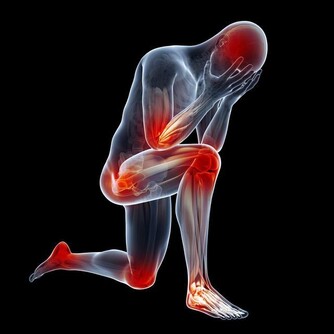

肝硬化晚期的症狀有哪些 1、全身症狀 疲倦乏力是肝硬化晚期症狀之一,肝硬化晚期症狀多半有皮膚乾枯粗糙,面色灰暗黝黑。 2、門靜脈高壓 表現為食道靜脈曲張,脾大和腹水,尤以食道靜脈曲張最危險。由於曲張靜脈的血管壁薄,很易破裂導致消化道大出血。 3、消化道症狀 食慾減退是最常見肝硬化晚期症狀,有時伴有噁心,嘔吐。一般表現為營養狀況較差,食慾明顯減退,進食後即感到上腹不適和飽脹、噁心、甚至嘔吐,肝硬化晚期對脂肪和蛋白質耐受性差,進油膩食物,易引起腹瀉。肝硬化患者因腹水和胃腸積氣而感腹脹難忍,晚期可出現中毒性鼓腸。 4、內分泌失調 肝硬化晚期時,肝臟的功能衰退更加明顯,直接導致雌性激素的滅活減少,雌激素分泌量上升,血液中含有大量的雌激素,同時伴有雄性激素受到抑制等現象。 5、出血傾向及貧血 肝硬化晚期常有鼻衄,齒齦出血,皮膚淤斑,胃腸粘膜糜爛出血,鼻腔出血,嘔血與黑糞,女性常有月經過多等症狀。 6、肝硬化腹水形成 肝硬化晚期腹水出現前常有腹脹,大量水使腹部膨隆,腹壁繃緊發高亮,狀如蛙腹,患者行走困難,有時膈顯著抬高,出現呼吸和臍疝。 肝硬化晚期飲食怎麼調理 1、晚期肝硬化患者以休息為主,絕對禁酒,飲食宜少鹽清淡,柔軟易消化,且營養要豐富。用適量動物蛋白對疾病恢復有利,絕對禁止葷食是錯誤的。只有重症患者有肝昏迷傾向或已發生肝昏迷者,短期內禁吃葷食是必要的,此時應以豆製品補充蛋白質的來源,避免進食堅硬或帶骨刺的粗糙食物,以及酸性飲料,調料等,以減少這些食物對食管黏膜的損傷。 2、宜保持大便通暢,在大便乾結時,可服用蜂蜜(乳)等製品,切勿用力排便,或者乾過重的體力活,否則會造成門靜脈壓力突然增加,引起食管靜脈曲張破裂出血。肝硬化患者免疫力低下,說其“弱不經風”並不過分,一旦感染髮熱,就足以使病情加重,故應積極預防感染。 3、需要指出的是,肝硬化用藥一定要得當。任何藥物都需經過肝臟代謝處理,雜藥亂投,有可能增加肝臟的負擔,甚至引起藥物性肝損害。所以,可用可不用的藥盡量不用,需要用的藥,要少而精,針對性要強。由此總結肝硬化藥物治療的原則是:不用藥、少用藥或用必要的藥! 4、肝髒病人雖然多吃蔬菜和水果有益,但應防止過多食用對肝臟有損害的食物,如扁豆、蘿蔔、蒜、洋蔥、菠菜等。因為這類食物中含有醚油類物質,這種物質對肝臟和膽囊會產生不良刺激。 小編提醒:肝硬化晚期的症狀已經很明顯了,這個時候很容易發覺病情,如果不想病情惡化,在肝硬化早期就得積極治療,防止病情惡化。最後,希望上述介紹能夠幫到大家。 |